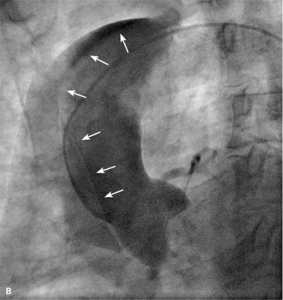

RYCINA 2. [A] Dyssekcja początkowego odcinka prawej tętnicy wieńcowej. [B] Progresja rozwarstwienia w kierunku łuku aorty.

Najczęstszym powikłaniem sercowym jest nagłe zamknięcie naczynia w czasie zabiegu lub wkrótce po nim. Dochodzi do niego zazwyczaj wskutek rozwarstwienia ściany poszerzanej tętnicy, zakrzepicy w stencie lub wystąpienia tzw. zjawiska no flow. W czasach przed upowszechnieniem się stentów dyssekcja zamykająca naczynie często prowadziła do pilnej operacji kardiochirurgicznej. Obecnie powikłanie to rzadko prowadzi do trwałej okluzji tętnicy wieńcowej z wyjątkiem tzw. dyssekcji spiralnej obejmującej bardzo długi odcinek, czasami nawet całe naczynie. Zazwyczaj implantacja jednego lub więcej stentów rozwiązuje problem. Dyssekcja może być trudna do zaopatrzenia, jeśli dojdzie do niej przed wprowadzeniem prowadnika lub gdy wprowadzenie stentu jest niemożliwe ze względu na krętość naczynia lub obecność zwapnień. Szczególnym rodzajem dyssekcji jest rozwarstwienie początkowego odcinka naczynia cewnikiem prowadzącym. Takie zdarzenie jest szczególnie niebezpieczne, jeśli dotyczy pnia lewej tętnicy wieńcowej (ryc. 1) i może się skończyć nagłym zgonem pacjenta. Czasami krew wnikająca do ściany naczynia blisko miejsca odejścia rozwarstwia opuszkę aorty. Taka dyssekcja może szybko objąć nawet całą aortę aż do jej podziału (ryc. 2A, B), co często wymaga pilnej interwencji chirurgicznej.